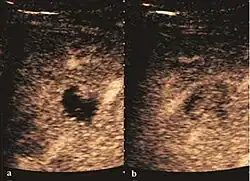

Encephaloid hepatocellular carcinoma (CEUS). Contrast tumor enhancement is observed on the left during arterial phase. The “wash-out” phenomenon can be seen on the right, during portal venous phase.

HCC appearance on 2D ultrasound is that of a solid tumor, with imprecise delineation, with heterogeneous structure, uni- or multilocular (encephaloid form). An "infiltrative" type is also described which is difficult to discriminate from liver nodular reconstruction in cirrhosis. Typically HCC invades liver vessels, primarily the portal veins but also the hepatic veins . Doppler examination detects a high speed arterial flow and low impedance index (correlated with described changes in tumor angiogenesis). The spatial distribution of the vessels is irregular, disordered. CEUS examination shows hyperenhancement of the lesion during the arterial phase. During the portal venous phase there is a specific "wash out" of ultrasound contrast agent (UCA) and the tumor appears hypoechoic during the late phase. Poorly differentiated tumors may have a stronger wash out leading to an isoechoic appearance to the liver parenchyma during portal venous phase. This appearance was found in approx. 30% of cases. The described changes have diagnostic value in liver nodules larger than 2 cm.